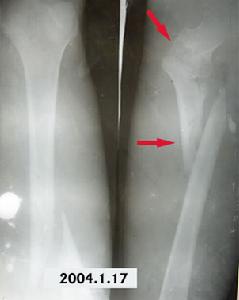

閉合性骨折臨床上閉合性骨折處有假甘關節活動,稱為閉合性骨折不化癒合或骨不連線。閉合性骨折不癒合多由於閉合性骨折端間較多軟組織,開放性閉合性骨折性創時去除的骨片較多造成的骨缺損,多次手術對骨的血液供應破壞較大等因素所致。閉合性骨折不癒合,不可能再通過延長治療時間而達到癒合,而需切除硬化骨,打通骨髓腔,修復骨缺損。一般需行植骨、內固定,必要時還需加用石膏繃帶外固定予以治療。

帶血管蒂的骨膜和骨移植以及吻合血管的游離骨膜和骨移植已成為治療閉合性骨折不癒合的重要方法。近年來也套用低頻電磁場治療無骨質缺損的閉合性骨折不癒合成功者,可使某些病例免去手術。閉合性骨折畸形癒合即閉合性骨折癒合的位置未達到功能復位的要求,存在成角、鏇轉或重疊畸形,畸形癒合可能由於閉合性骨折復位不佳,固定不牢固或過早地拆除固定,受肌肉牽拉,肢體重要和不恰當的負重的影響所致。

(2)定期X線拍片觀察內固定物的位置及骨折癒合情況。內固定物有滑出、變位者應設法糾正,癒合延遲者應予以確實外固定。